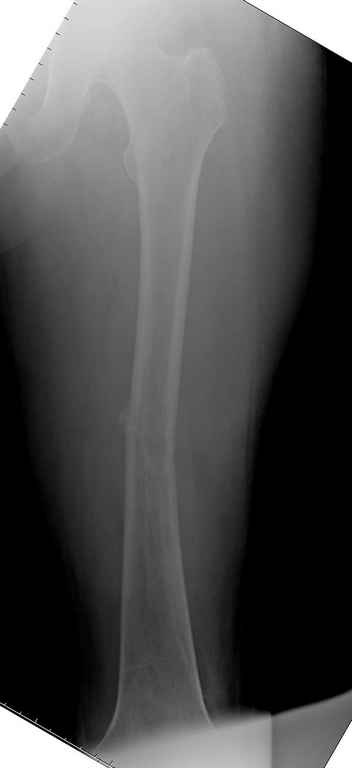

В зависимости от характера опухоли некоторые патологические переломы имеют риск кровотечения во время операции. Множественные литературные данные подтверждают, что надо проявить осторожность при интрамедуллярном остеосинтезе при неизвестных опухолях, особенно где имеется подозрение на Renal Cell Carcinoma. (RCC- hypernephroma) http://www.bonetumor.org/tumors/pages/page64.html

Со слов, больная ничем не болела, только последние 3 месяцев чувствовала боли в бедренной области. КТ брюшной полости подтвердил увеличенную правую почку. (5-6)

Для предупреждения кровотечения во время рассверливания, за день до операции провели эмболизацию сосудов питающий метастаз. http://radiology.rsnajnls.org/cgi/reprint/150/3/673.pdf (7-11, 12-15-16)